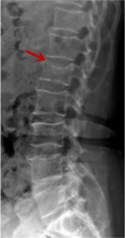

利器一:X線/DR

腰椎X線片作為最基礎(chǔ)的影像檢查手段,利于X線穿透人體組織后成像,以其快捷、直觀、價格低廉的特點,X線檢查主要包括腰椎正側(cè)位、雙斜位以及過伸過屈位。主要用于觀察腰椎骨骼的情況,如椎體是否有骨折、骨質(zhì)增生程度、生理曲度的變化、椎體移位的情況等。然而,X線檢查也有它的局限性,無法判斷是骨折的新舊,對于椎體內(nèi)部結(jié)構(gòu)和周圍肌肉韌帶組織(如脊髓神經(jīng)、椎間盤、韌帶等)的顯示不佳,另外X線作為有輻射檢查,孕婦及嬰幼兒謹慎選擇。

箭頭提示腰1椎骨折

箭頭提示腰3椎體滑脫